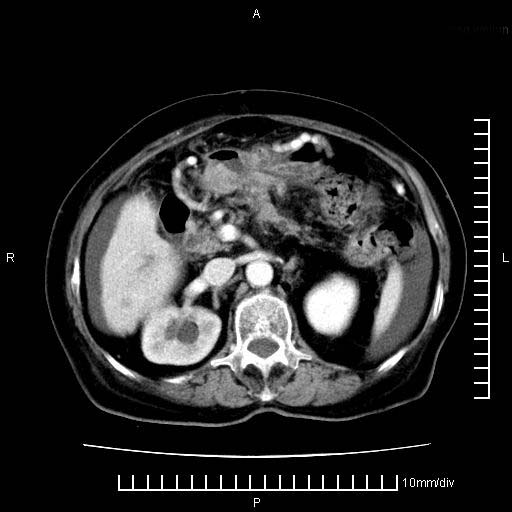

标题: CT28280:腹部增强:女性,80岁

上腹疼痛月余,外院核磁诊断胰腺癌。现临床示右下腹可明显触及包块,可片子上怎么没有看到?

1.胰腺颈体部癌。

2。腹腔积液。

3。右胸腔积液,伴右肺下叶部分萎陷。

4。右肾盂囊肿。

胰腺体部癌累及周围器官,腹膜、粘连

1。胰腺ca伴腹膜腔转移

2。肝左叶低密度灶,考虑转移可能

胰腺体部癌累及周围器官,腹膜、粘连,临床摸到的可能是粘的组织

胰腺结构模糊,胰尾部见囊性包块,周围脂肪密度增高,左肾前筋膜增厚,胸水、腹水。不符合胰腺ca伴腹膜腔转移。考虑胰腺炎伴假性囊肿形成、胸腹腔积液。

右肾盂囊肿。

1)考虑胰腺癌并胰腺假性囊肿形成。2)肝内低密度灶,不排除转移。3)右肾盂积水。4)腹水。5)右侧胸腔积液并右肺下叶部分膨胀不全。